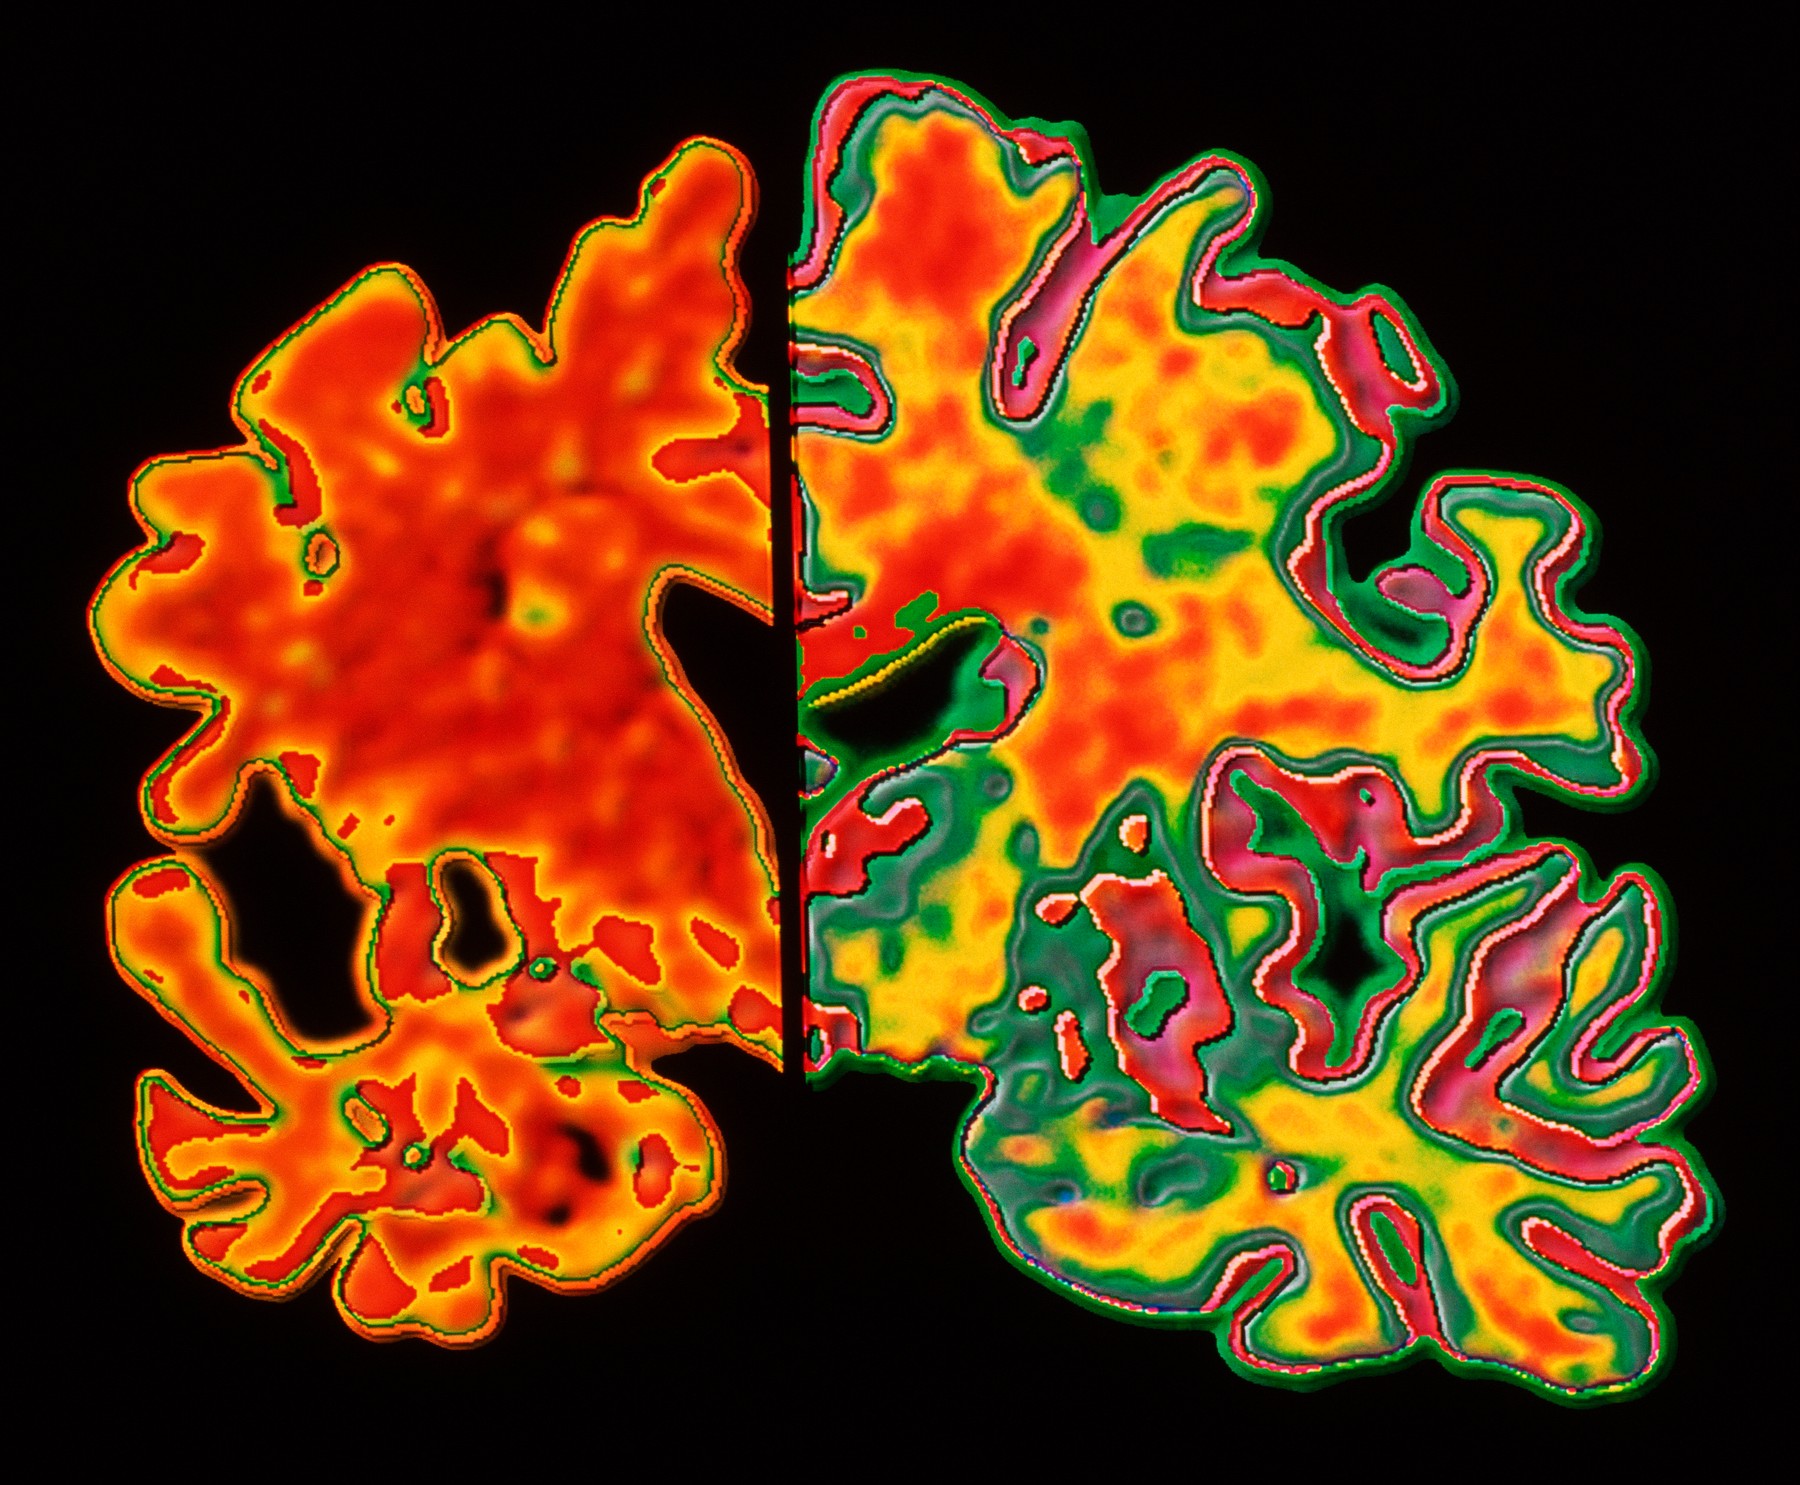

Poleg koristi za umske sposobnosti je študija pokazala še, da je bilo zdravilo povezano s 50 odstotkov manjšo izgubo volumna v več predelih možganov. Te ugotovitve dajejo upanje, da bodo večja testiranja, ki jih izvaja proizvajalec Ozempica Novo Nordisk, uspešna, je Carrillo povedala za CNN.

Pri Alzheimerjevi bolezni se v možganih postopoma nenormalno kopičita dve ključni beljakovini, amiloid beta in tau, zaradi česar možganske celice odmrejo, možgani pa se skrčijo. To povzroča izgubo spomina in vse večjo nezmožnost opravljanja vsakodnevnih opravil.